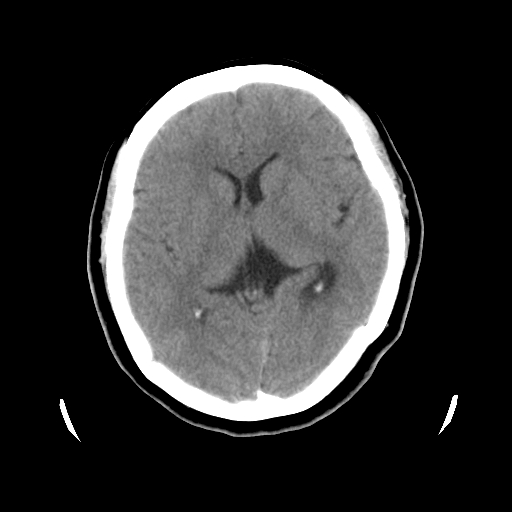

以下是引用cgf在2010-1-3 17:53:00的发言:[br]此病例多考虑:透明隔发育异常 透明隔囊肿可能性大;右侧基底节区(尾状核头)小片状低密度影考虑陈旧性腔梗[br][br]透明隔发育异常:包括透明隔间腔(第五脑室)、韦氏腔(第六脑室)、透明隔囊肿、透明隔缺如;前两者属于正常变异,后两者属于发育畸形;[br]透明隔间腔向下扩张形成韦氏腔;[br]有时透明隔间腔与透明隔囊肿很难鉴别;透明隔间腔间距一般不超过0.5cm,间距大于0.5cm时应考虑透明隔囊肿;[br]透明隔缺如为两侧脑室间隔缺如、融合成单脑室畸形,可伴有智力发育异常;[br][br]

以下是引用liaoqiang在2010-1-3 16:04:00的发言:[br]考虑侧脑室脉络丛囊肿?不除外变异的威氏腔。

以下是引用江广1996在2010-1-3 20:17:00的发言:[br]考虑变异的威氏腔。不除外侧脑室脉络丛囊肿.[br]透明隔囊肿大多数偏前,在侧脑室前角之间。